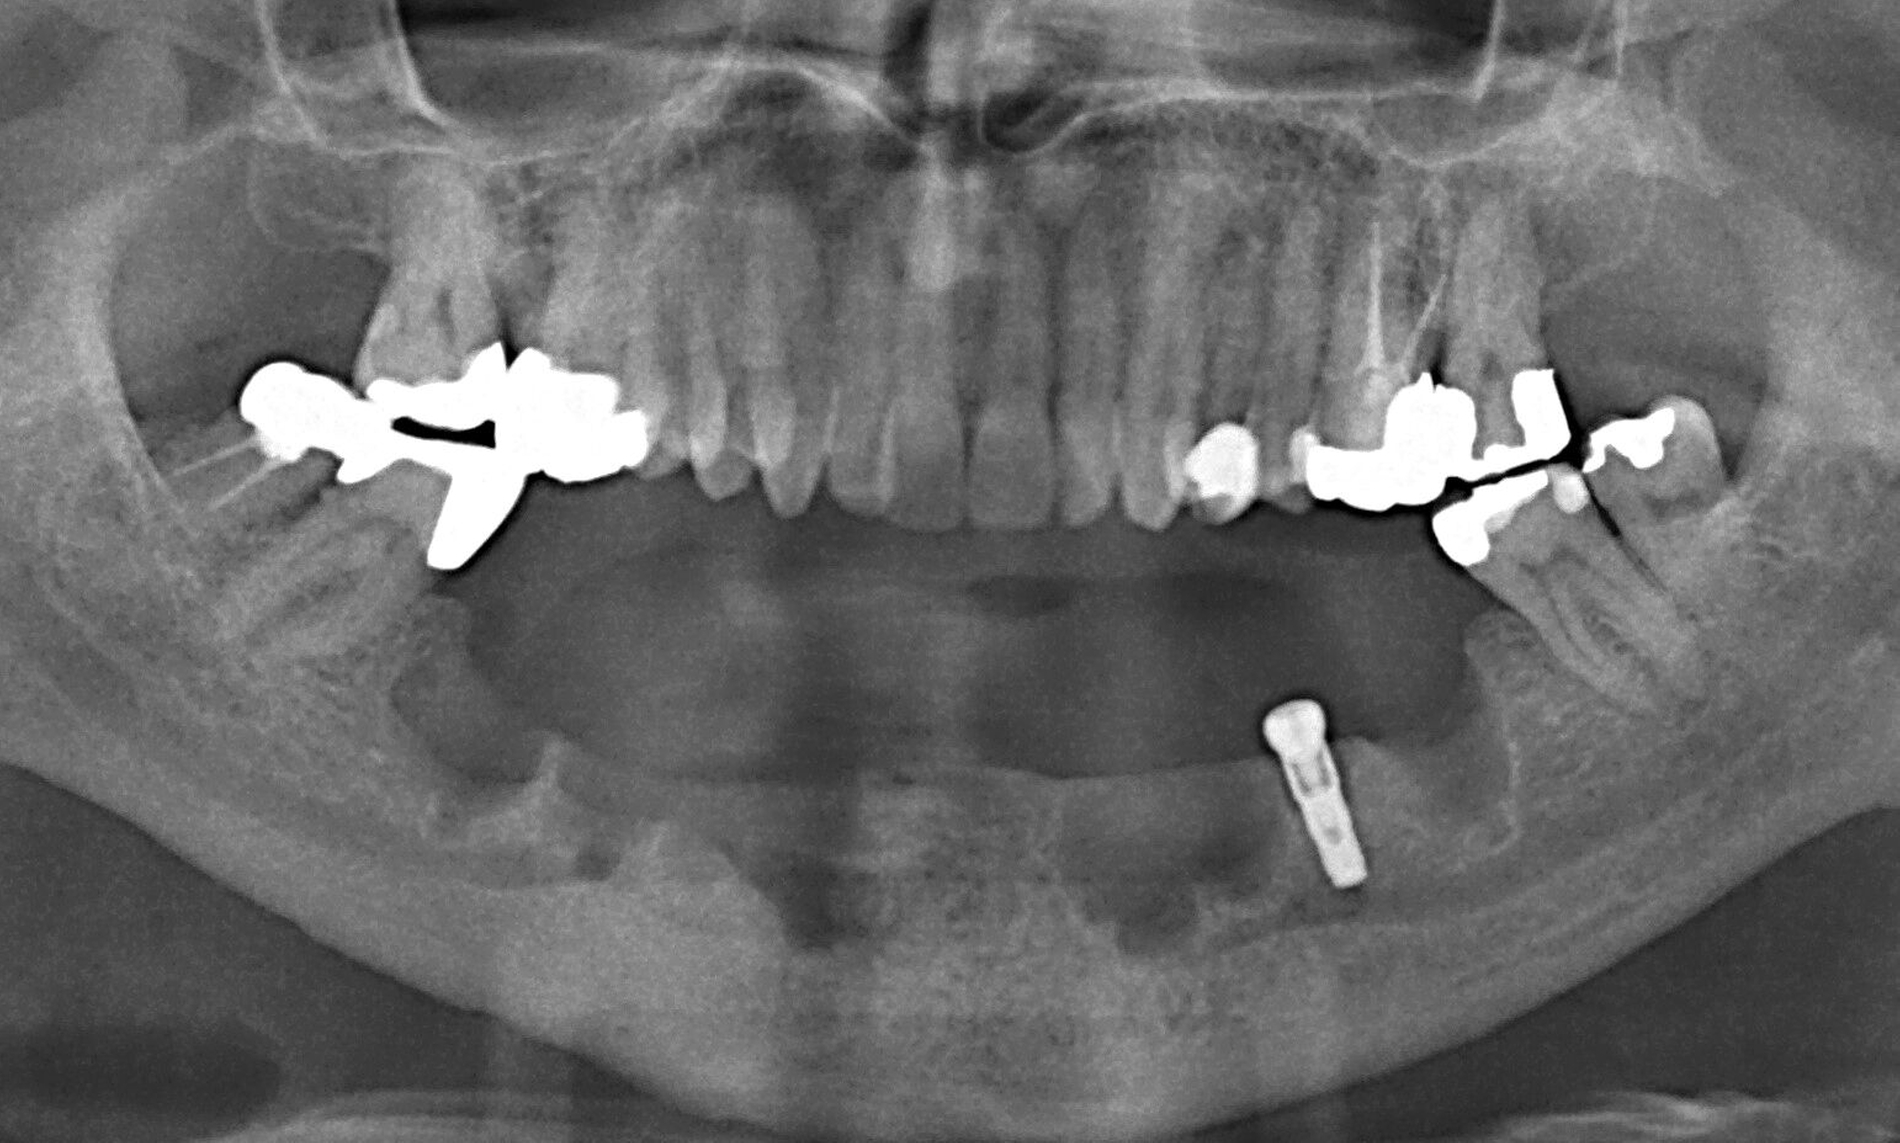

Nachdem der Patient bei einem Berufsunfall mit Ausnahme der zweiten Molaren und der Weisheitszähne alle Zähne im Unterkiefer verloren hatte, erfolgte 1996 im Alter von 44 Jahren die definitive Lückenversorgung. Hierzu wurden eine verschraubte Brückenkonstruktion (044-034-043-044) sowie zwei verblockte Kronenpaare auf insgesamt acht Implantaten eingesetzt. Nach sieben Jahren Tragedauer wurde an mehreren Implantaten röntgenologisch ein Knochenabbau festgestellt. Verkürzte Kontrollintervalle mit professionellen Zahnreinigungen und intensiven Instruktionen zur Interdentalhygiene konnten nicht verhindern, dass nach weiteren sieben Jahren Anfang 2011 der Knochenverlust an den meisten Implantaten auf 50 bis 80 Prozent zunahm (Abb. 1a).

Die Entscheidung zur Explantation fiel wegen des beschleunigten Knochenverlusts und der extrem erschwerten Bedingungen für eine effektive Mundhygiene im Bereich der Implantate mit Sondierungstiefen bis zu 12 mm (Abb. 1b und 1c). Unter Lokalanästhesie wurden sieben der acht Implantate mit einem passenden Trepanbohrer mit 0,1 mm Aufmaß im Vergleich zum Außendurchmesser der Implantate umbohrt, anschließend mit einem kleinen Rasparatorium gelockert und dann mit einer Arterienklemme entfernt. Entscheidend für die Eignung der Trepanbohrer war die Längenmarkierung, um eine Nervverletzung bei der Entfernung der sehr tief gesetzten Seitenzahnimplantate zu vermeiden (Abb. 1d und 1e). Eine ausgedehnte Lappenbildung konnte durch dieses Vorgehen vermieden werden.

Eine präoperativ vorbereitete Interimsprothese, die über zwei gegossene Bonwill-Klammern sowie das verbliebene Implantat in regio 35 stabil abgestützt war, diente gleichzeitig als Verbandsplatte (Abb. 1f). Auf eine Glättung scharfer Knochenkanten oder die Nivellierung der Kieferkämme wurde verzichtet, um einen iatrogenen Knochenverlust zu vermeiden und das regenerative Potenzial des verbliebenen Knochens zu nutzen (Abb. 1g). Bereits bei der röntgenologischen Kontrolle nach drei Monaten war eine deutliche Zunahme des Knochens im Bereich der alten Implantatpositionen zu erkennen (Abb. 1h). Eine Nachimplantation von vier Implantaten in den Positionen 32, 34, 42 und 44 erfolgte neun Monate nach der Explantation und einer vorangegangenen Verbesserung der Weichgewebsbedeckung durch multiple freie Schleimhautransplantate vom harten Gaumen. Die knöcherne Regeneration unter der gut abgestützten Modellgussprothese verlief so günstig, dass sich der vertikale Höhenverlust des Alveolarkamms im Bereich der gescheiterten Implantate auf circa 2 mm begrenzen ließ. Das zur Entlastung der Kieferkämme und der einheilenden Implantate außerordentlich hilfreiche Implantat in regio 35 wurde erst nach dem Einheilen der nachgesetzten Implantate entfernt. Nach der Einheilzeit der Implantate von weiteren drei Monaten wurde eine kombiniert Zahn/Implantat-gestützte Teleskopprothese mit intraoral verklebten Galvano-Sekundärkronen eingegliedert (Abb. 1k bis 1m). Inzwischen ist diese, wie eine herausnehmbare Brücke abgestützte UK-Prothese seit zehn Jahren funktionstüchtig ohne Zeichen einer Periimplantitis an den vier Implantaten.